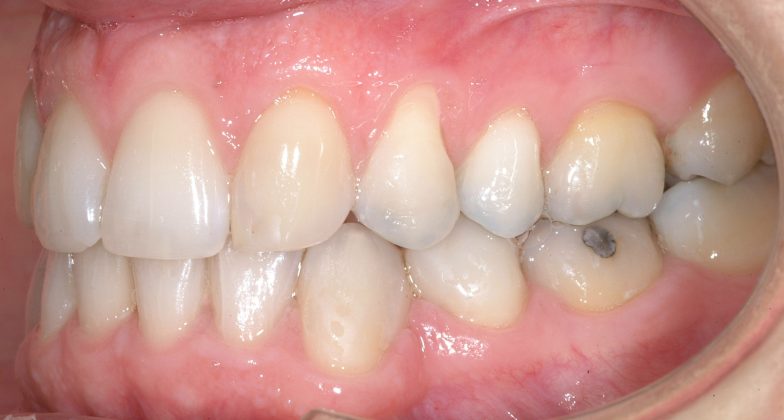

Il protocollo terapeutico ha previsto l’estrazione del primo premolare inferiore sinistro (3.4) e del primo superiore destro (1.4), l’applicazione di una apparecchiatura fissa linguale 2D e di una meccanica asimmetrica di ancoraggio e movimento ortodontico a entrambe le arcate (Figure 3a-b).

Il trattamento è iniziato con l’estrazione dei due premolari in unica seduta in anestesia locale e l’applicazione simultanea, dopo una settimana, della apparecchiatura linguale inferiore e superiore, non essendoci problemi di overbite e potenziali interferenze in occlusione tra l’apparecchiatura superiore e i frontali inferiori. All’arcata superiore è stata effettuata una iniziale chiusura dello spazio estrattivo con forze molto leggere in ancoraggio medio su arco .014” Nichel-Titanio e successivamente .016” Nichel-Titanio, bondato in prima fase per maggior stabilità direttamente sulla superficie mesiale di 2.4.

Nota tecnica: il movimento iniziale di distalizzazione della corona di 1.3 mediante tipping distale (vista la posizione radicolare iniziale) è stato ottenuto con una catenella elastica leggera inserita su 1.6, 1.5 e ancorata su 1.3, abbracciando per maggior controllo l’aletta disto-occlusale e quella gengivale del bracket linguale.